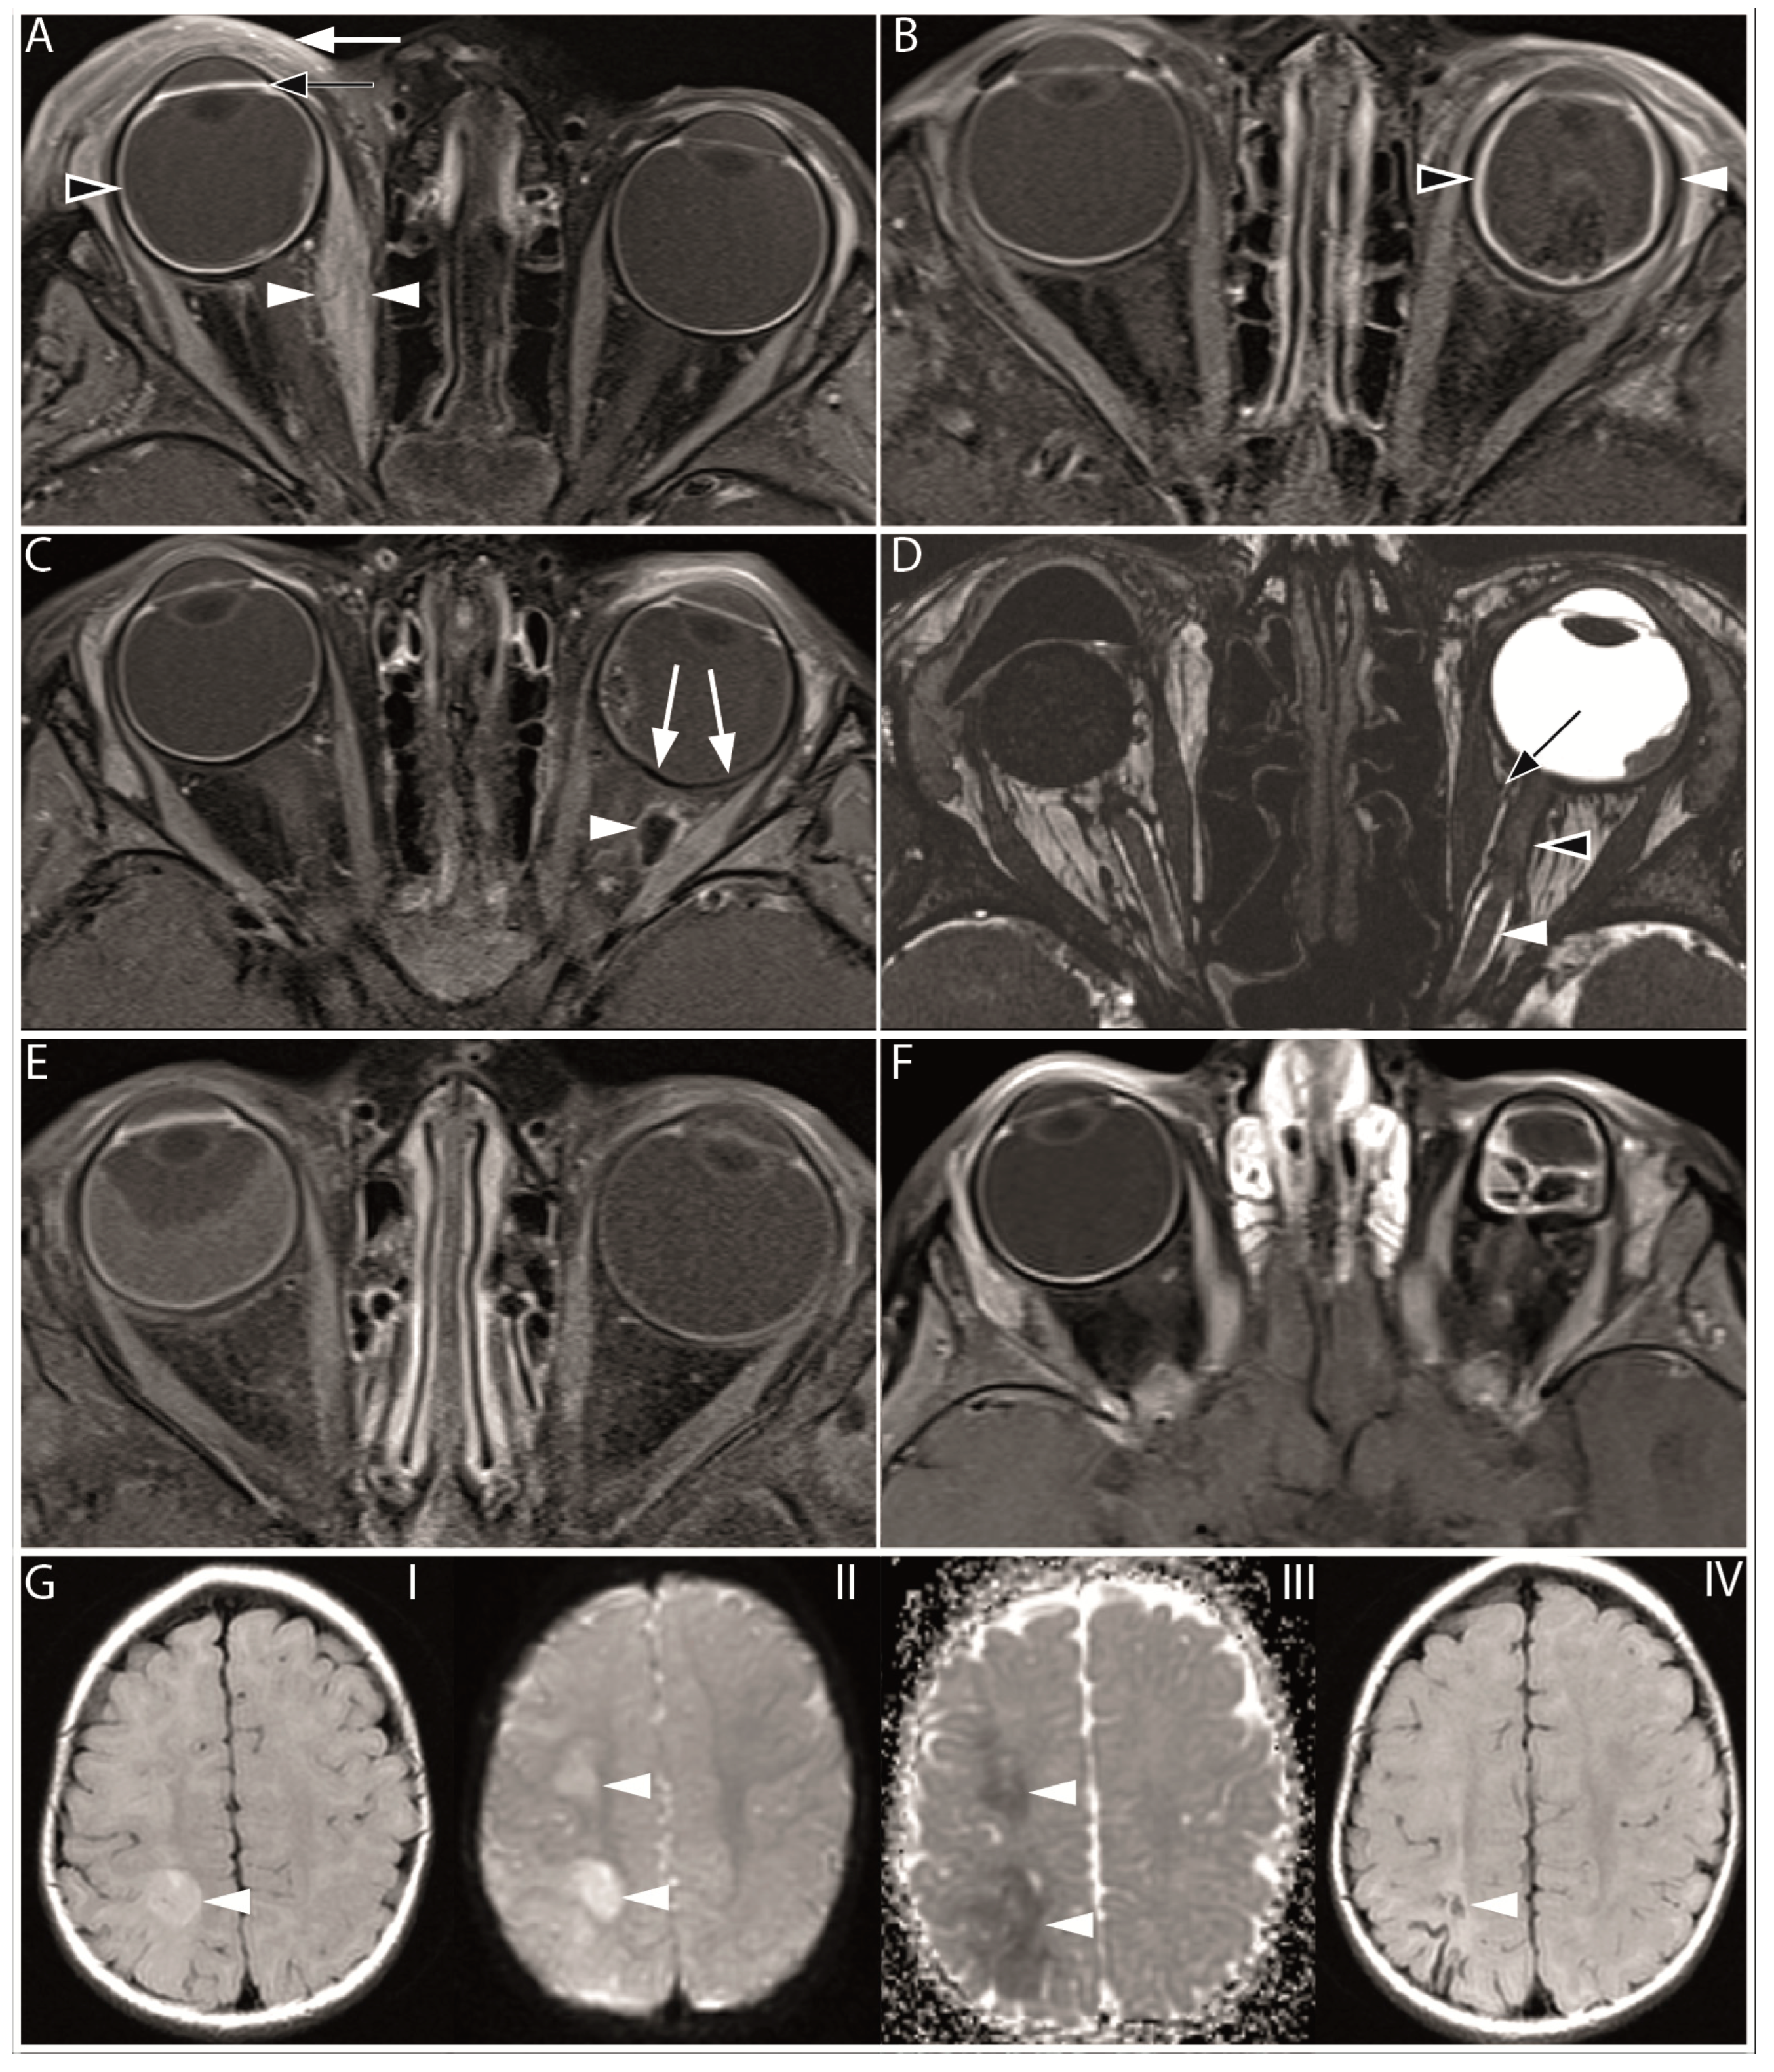

3.2. Qualitative Imaging Features

| Feature | n of events/n of eyes, % (95% CI) | n of events/n of eyes, % (95% CI) |

| Ocular | ||

| Retinal detachment | 87/184, 47 (38–58) | 82/234, 35 (29–42) |

| Subretinal hemorrhage | 43/182, 24 (17–31) | 37/234, 16 (11–21) |

| Vitreous hemorrhage | 3/183, 2 (0–5) | 5/234, 2 (1–4) |

| Enhancement of the anterior eye segment | n/a | 55/231, 24 (18–30) |

| Choroidal infarction | n/a | 24/233, 10 (7–15) |

| Choroidal thickening | n/a | 62/234, 27 (21–33) |

| Orbital (Preseptal space) | n/a | |

| Palpebral inflammation (cellulitis) | n/a | 29/231, 13 (9–18) |

| Orbital (Postseptal space) | n/a | |

| Extraocular muscle fibrosis | n/a | 1/234, 0 (0–2) |

| Extraocular muscle inflammation (myositis) | n/a | 68/233, 29 (23–35) |

| Orbital fat enhancement (cellulitis) | n/a | 41/232, 18 (13–24) |

| Orbital fat necrosis | n/a | 2/232, 1 (0–7) |

| Optic nerve enhancement | n/a | 15/233, 6 (4–10) |

| Perineural optic nerve fibrosis | n/a | 1/226, 0 (0–2) |

| Intracranial | ||

| Cerebral infarction | n/a | 3/234, 1 (0–4) |